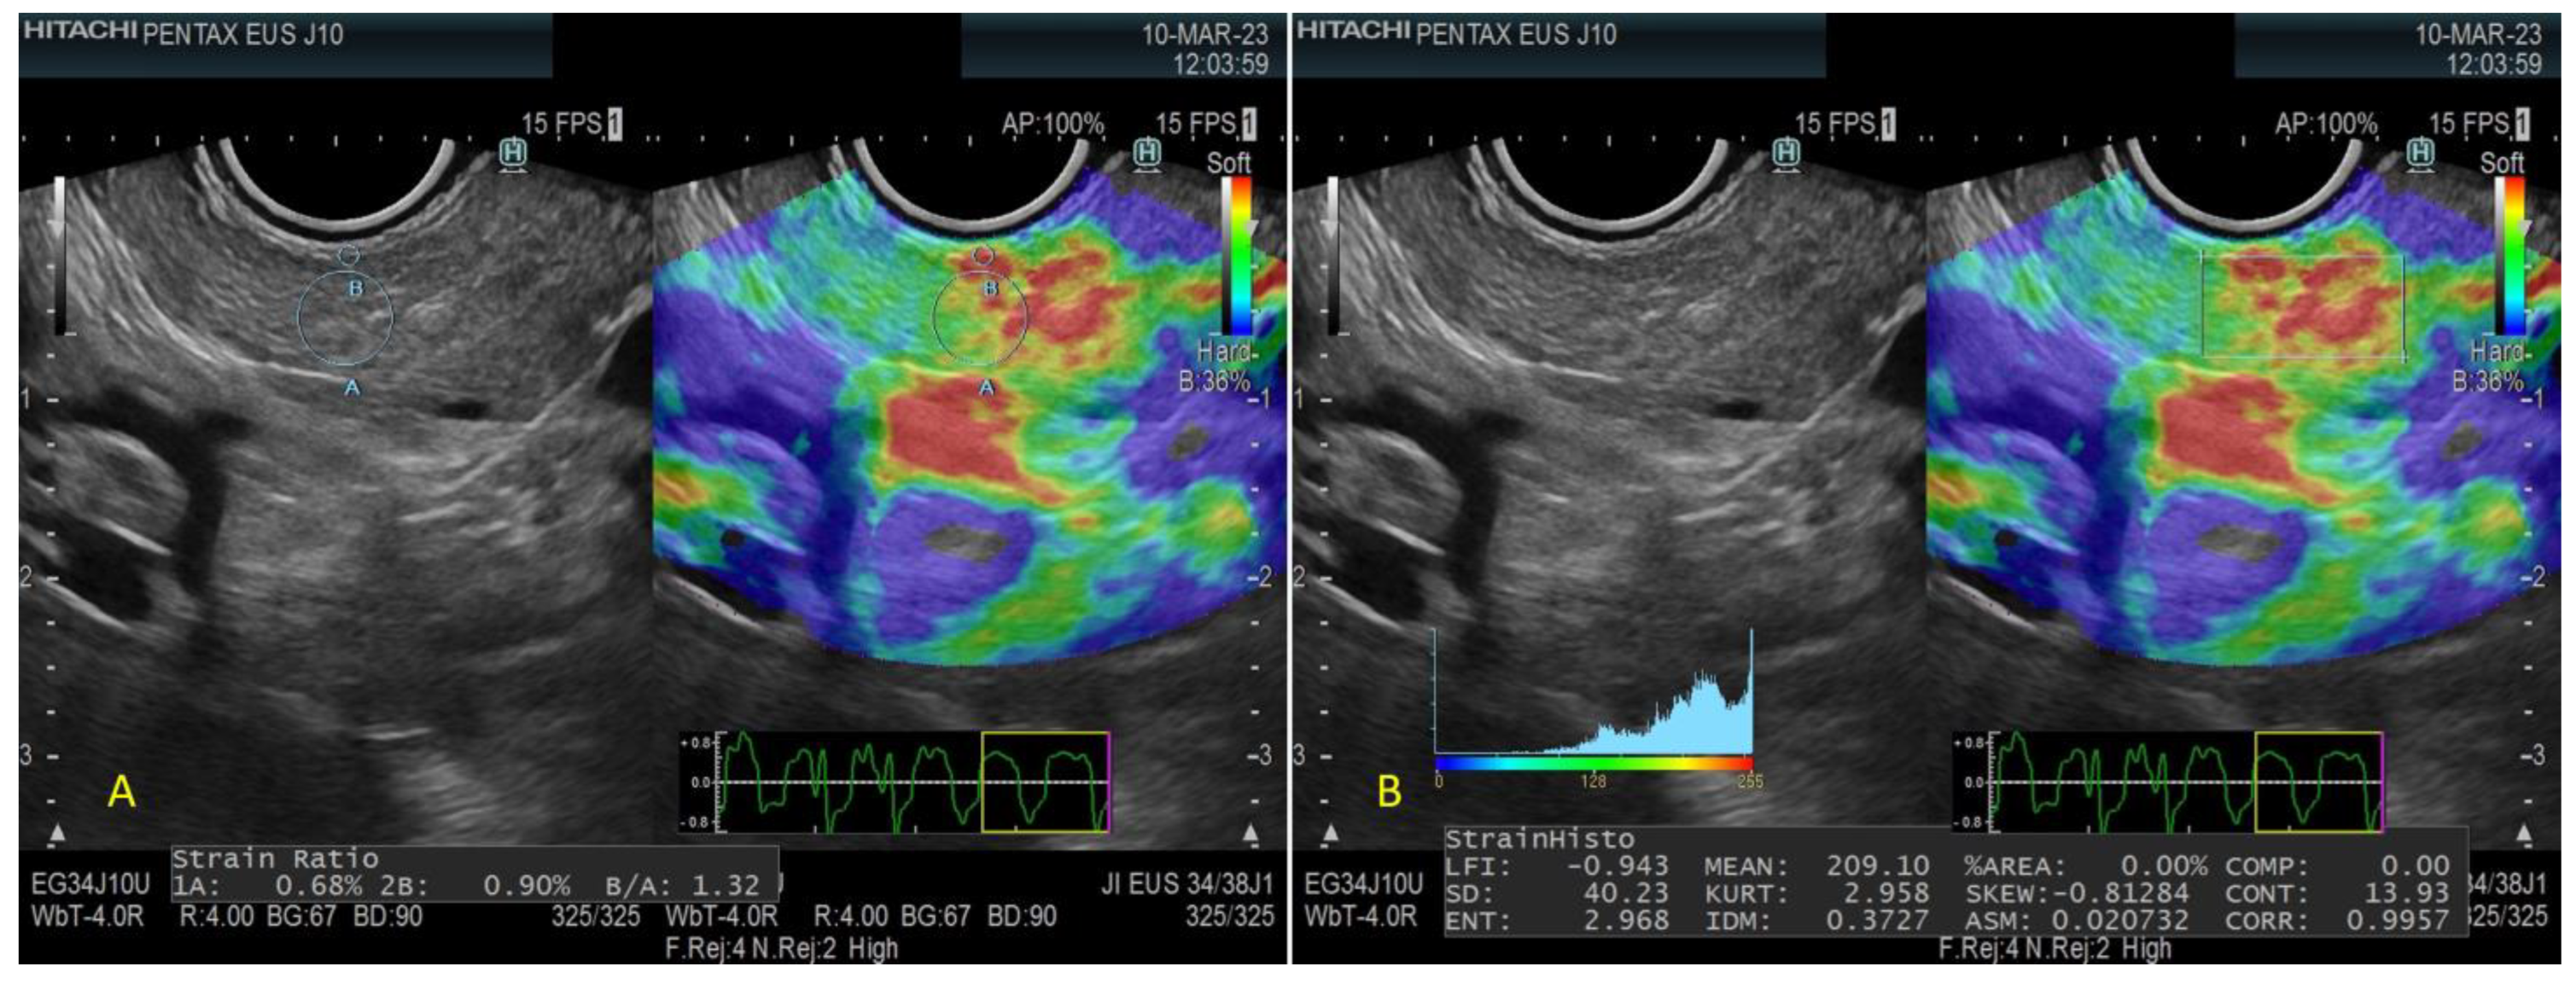

- Quantitative Strain Elastography

- Strain Histogram

- Strain ratio